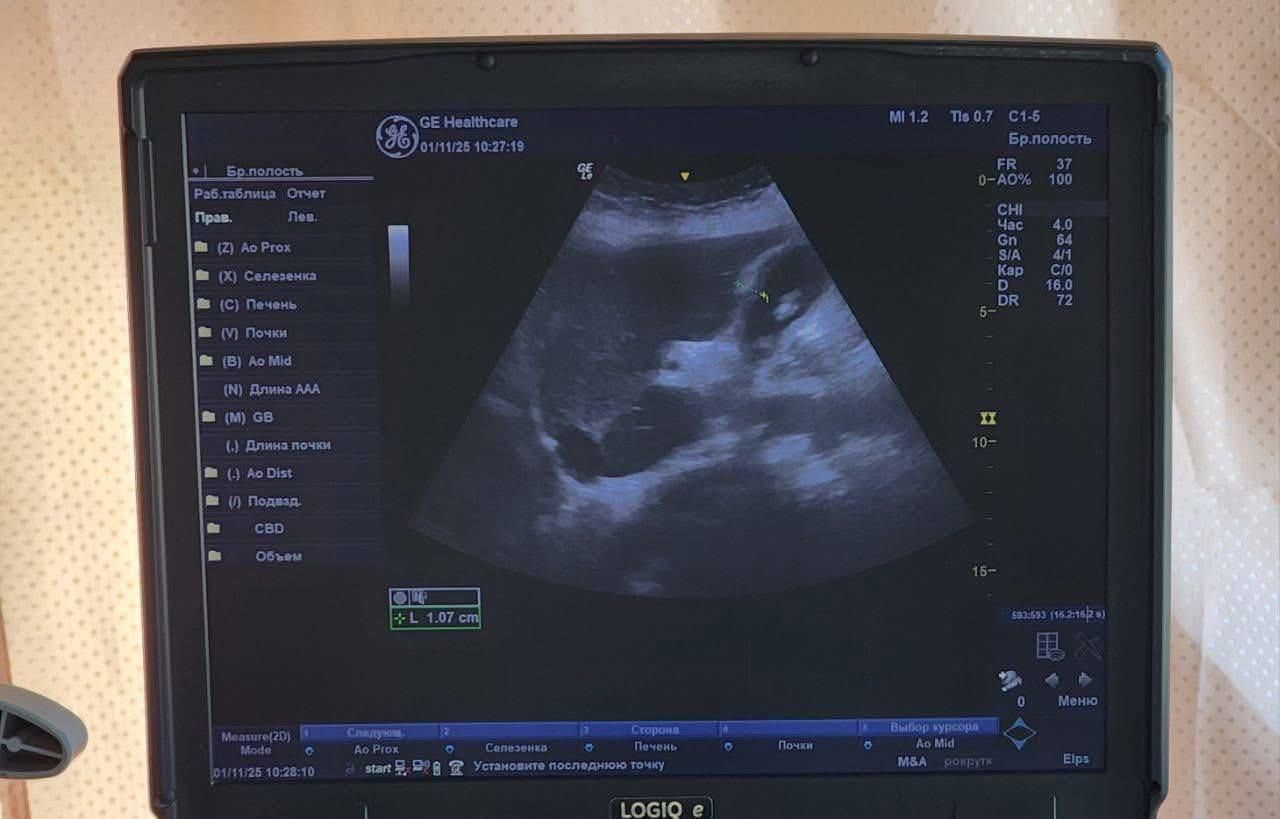

🔹ультразвукову діагностику (УЗД);